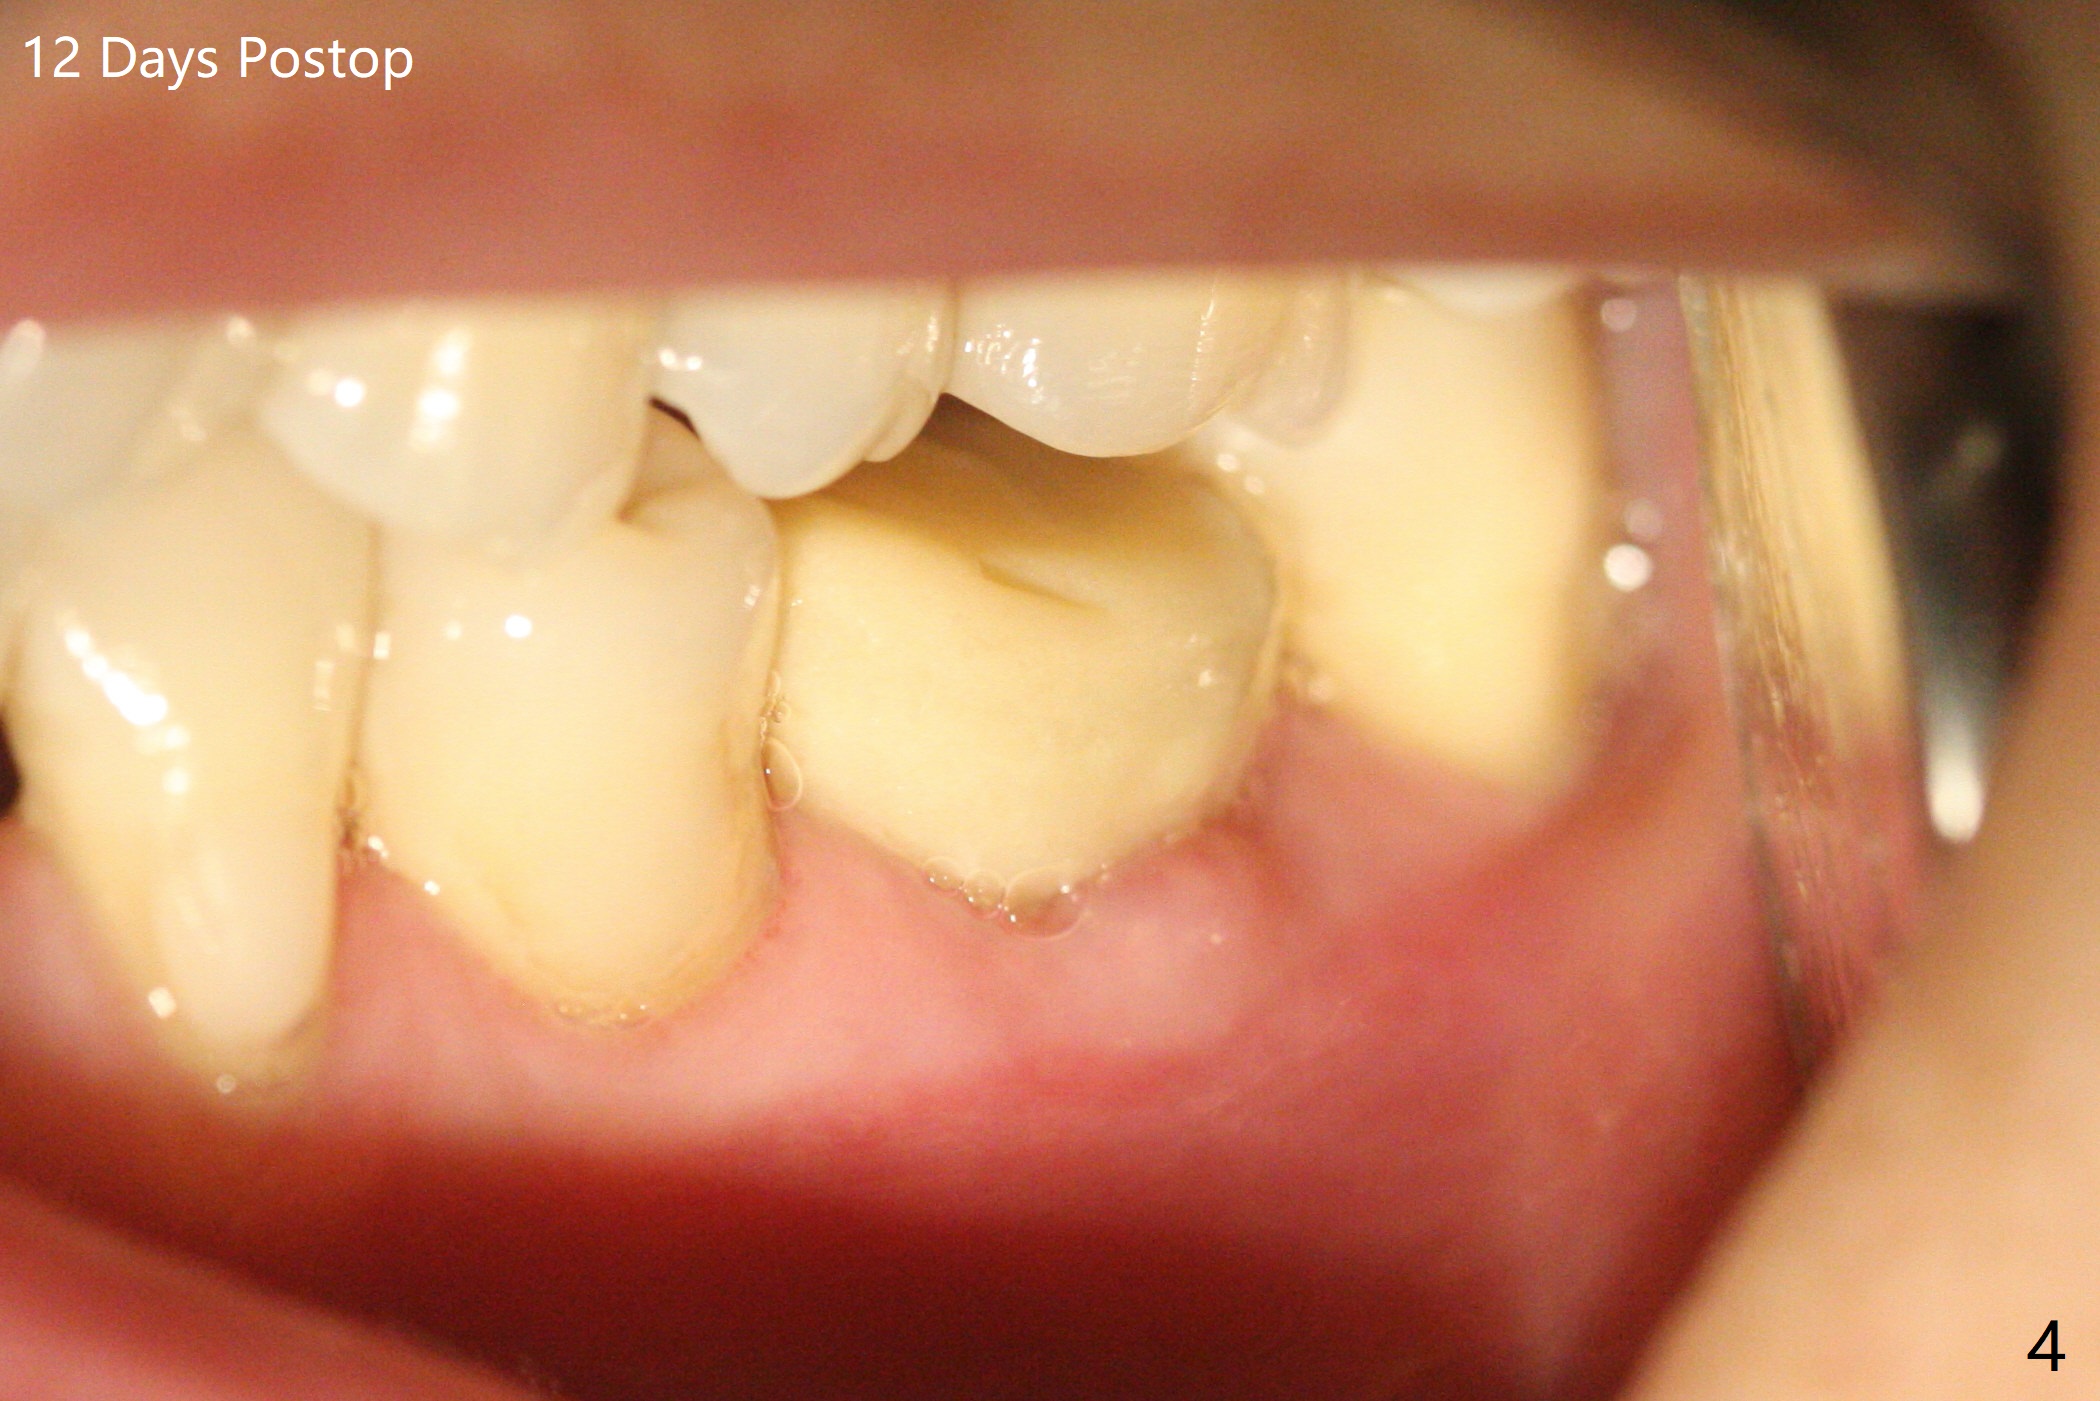

左下第一磨牙拔除后,放置导板,最细钻头到深度,没有偏移: 在中隔正中(图一),细短植体植入后基本保持在中隔之中(图二),扭力~30Ncm,在近中,远中剩余牙槽窝植骨后(图二:*),安置修复基台。制作临时牙冠后,在基台周围再次放置骨粉(图三)。术后7天牙周敷料脱落,12天复查时,临时牙冠周围软组织(角化龈,龈乳头)正常(图四)。